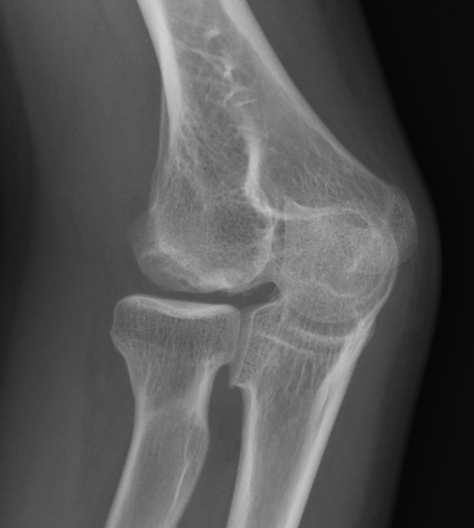

Xray

Kijowski et al Skeletal Radiology 2005

- 50% of capitellar OCD not identified on xray

Localized flattening and translucency Lucency in capitellum